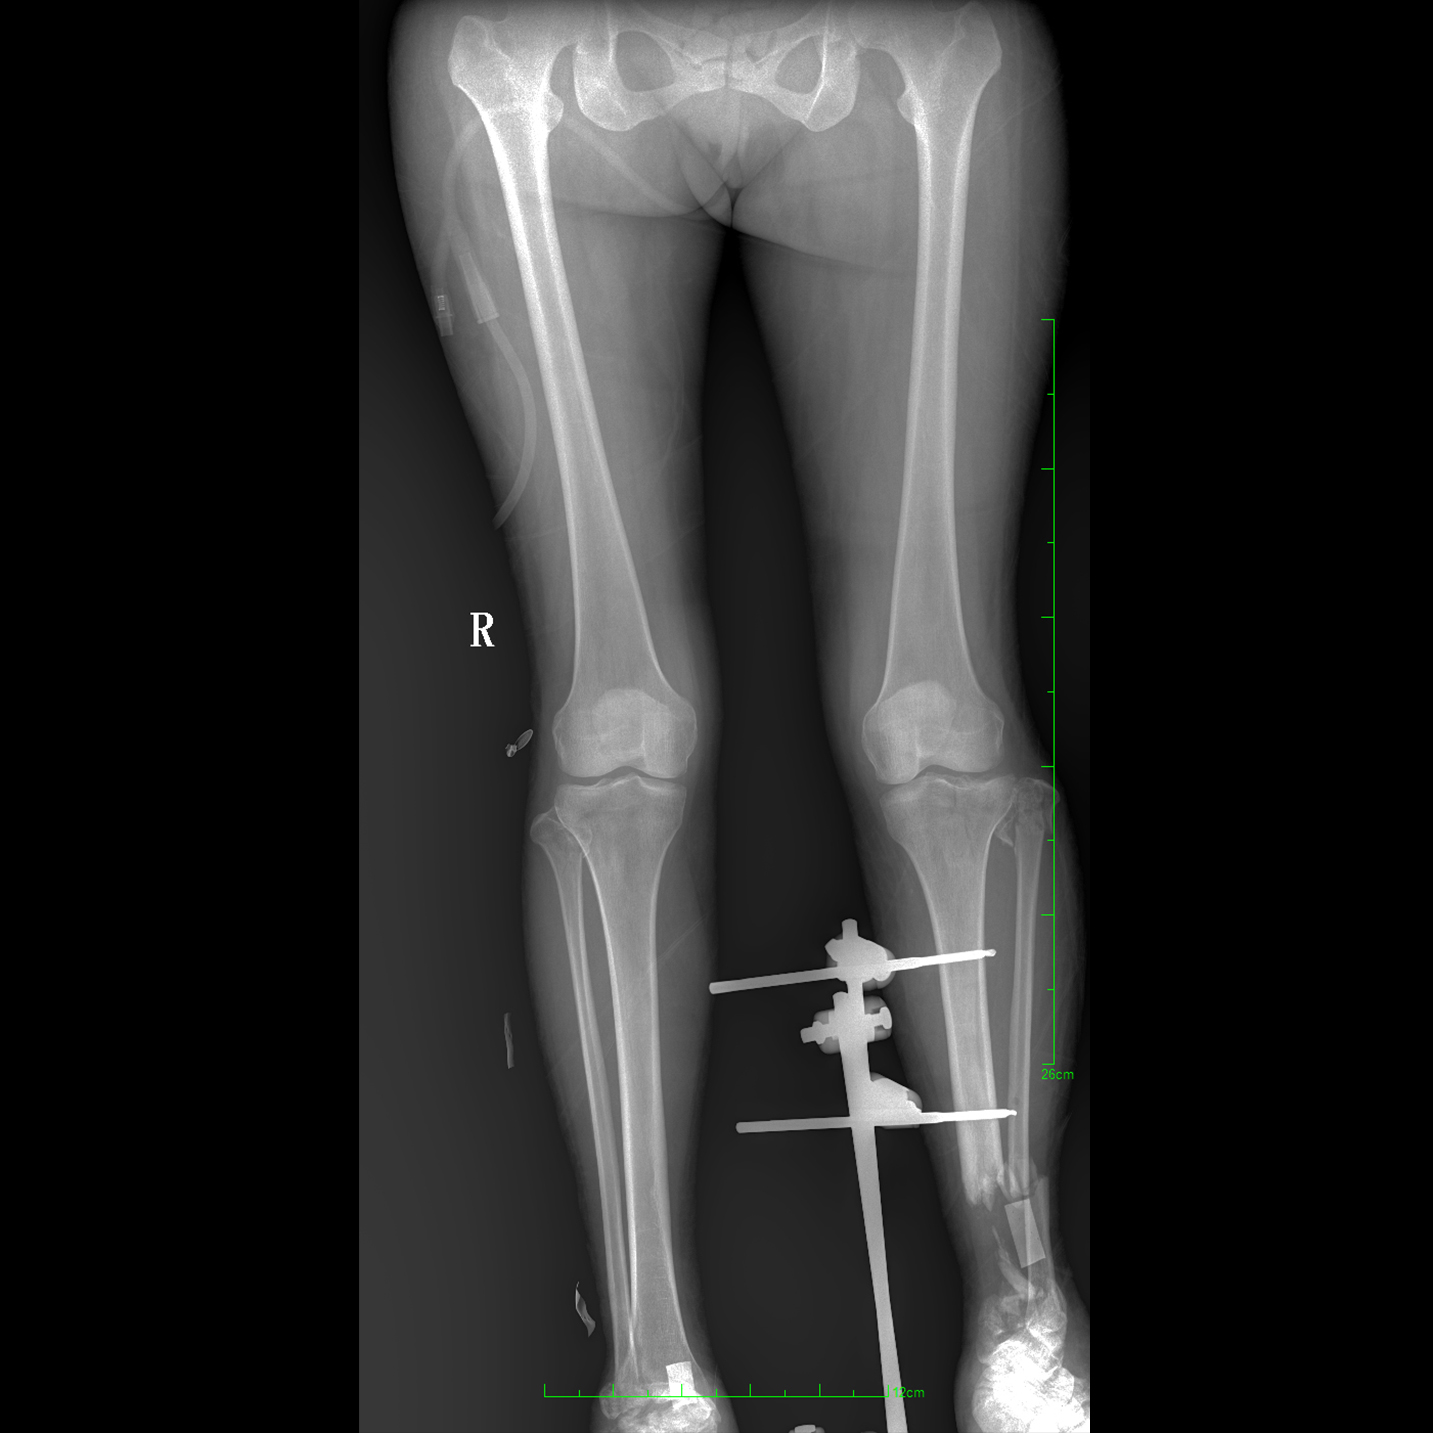

支持全脊柱攝影、雙下肢攝影、脊髓造影、復(fù)雜創(chuàng)傷、人工關(guān)節(jié)置換、關(guān)節(jié)損傷的修復(fù)重建等大視野臨床應(yīng)用

17"*34"有效視野,一次成像不拼接。相較于多張攝影再軟件拼接的DR設(shè)備,PLX8600解決了拼接圖像存在密度不均勻,拼接處圖像配準(zhǔn)和放大效應(yīng)等問(wèn)題,給臨床帶來(lái)了大視野影像解決方案,可一次性覆蓋全脊柱或雙下肢影像。